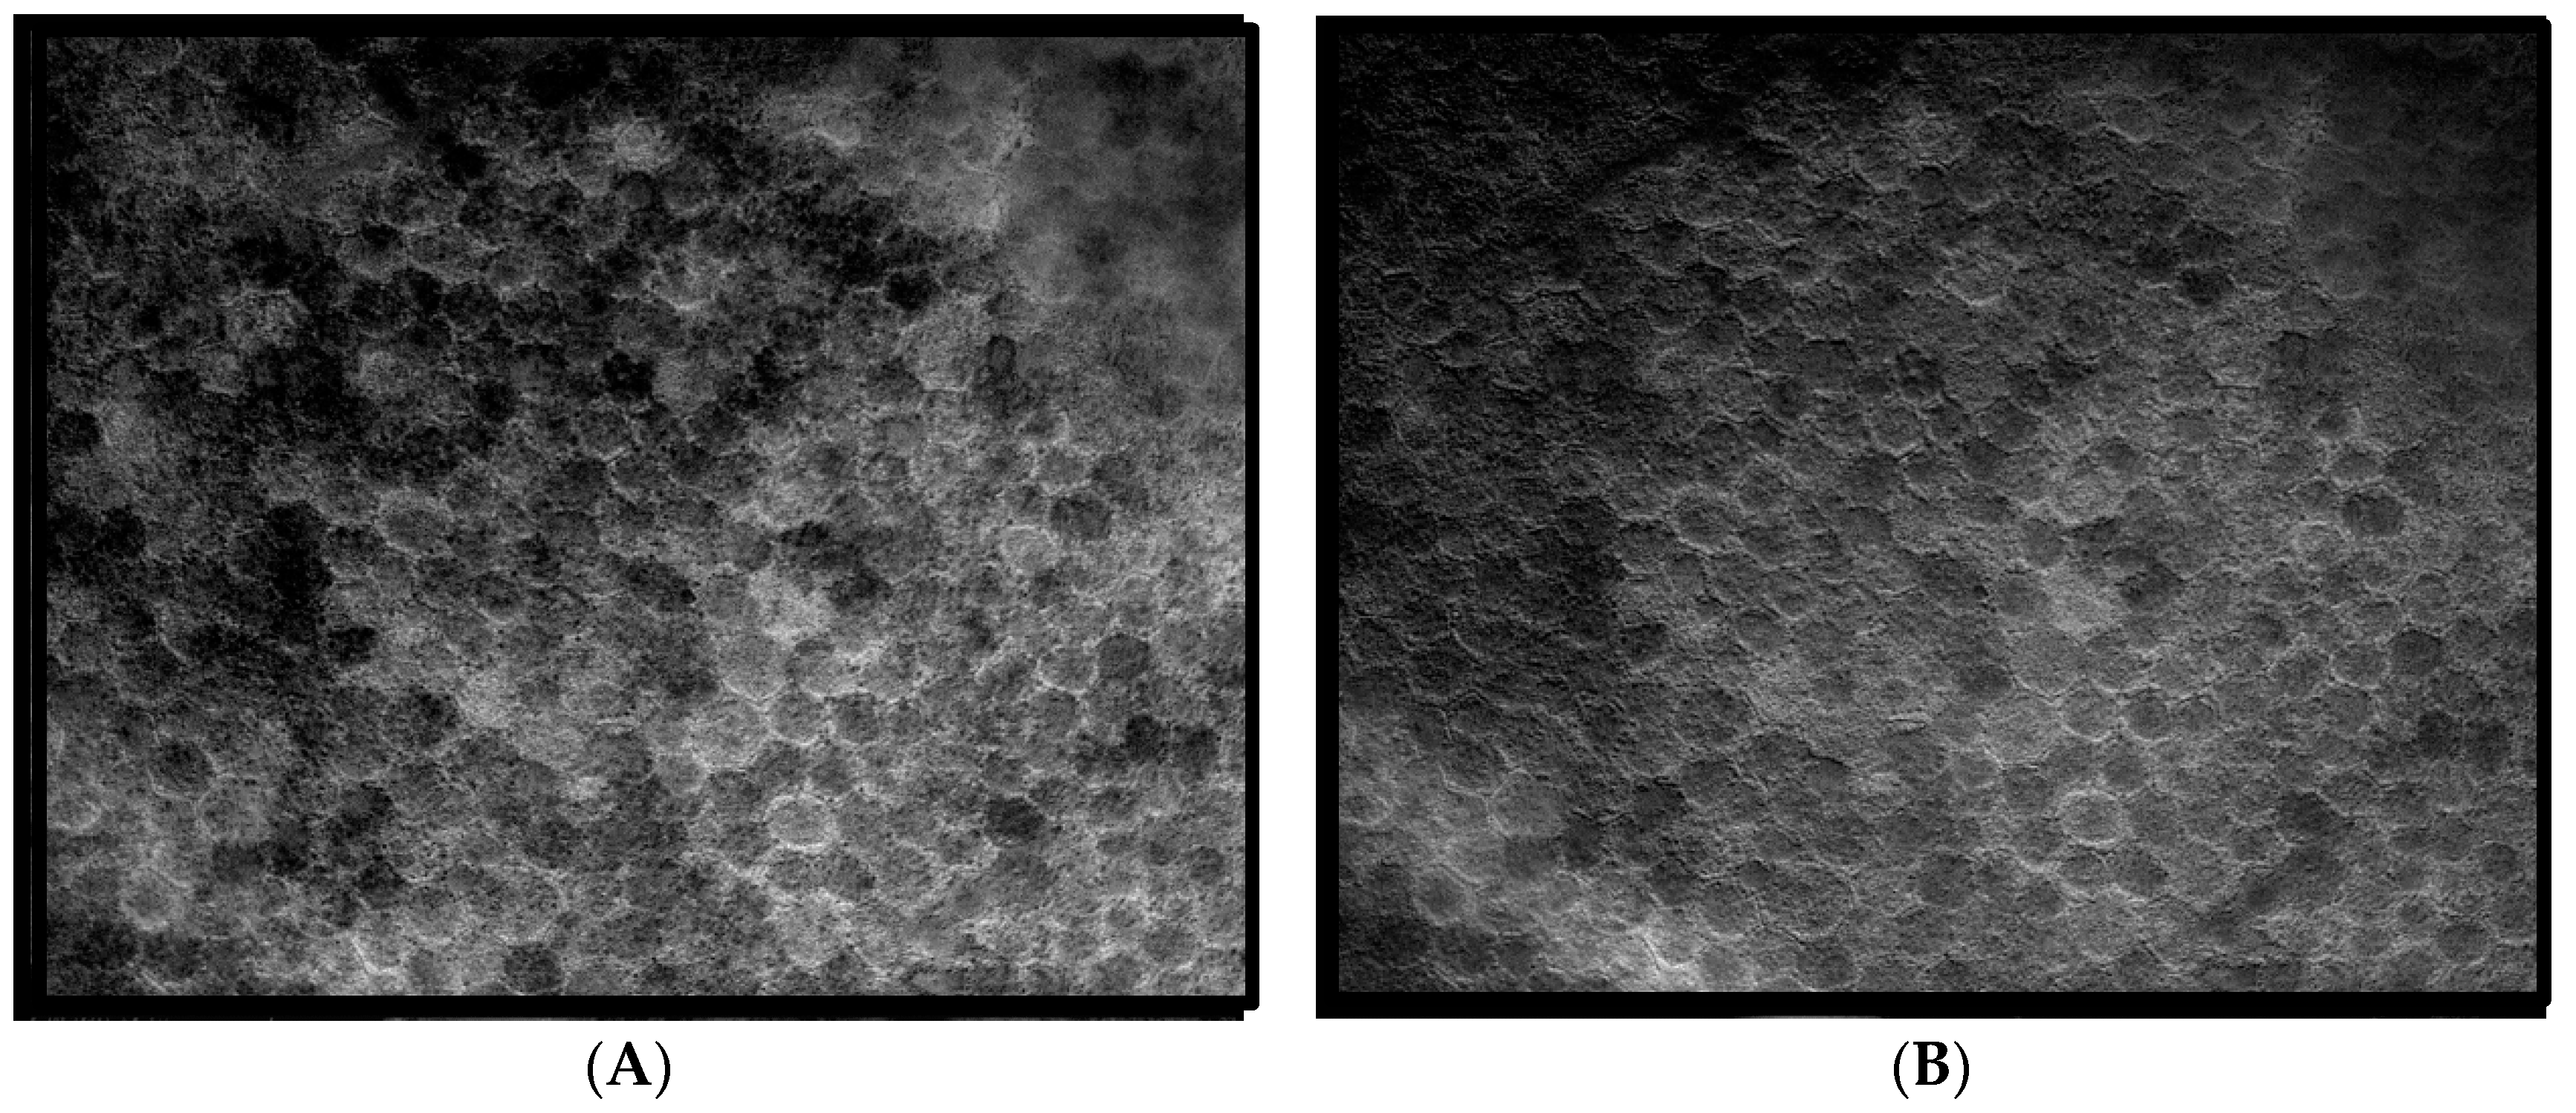

The same fluorophore families were recovered as previously described [14], that is, three spectra (S1, S2, and S3), with S1, S2 attributable to RPE LF and S3 attributable to RPE MLF and one spectrum (SDr) attributable to drusen and sub-RPE diffuse deposits. However, adding a third excitation appeared to improve the spatial and spectral recovery of the NMF algorithm. Spatially, abundance images seemed to suggest more information about fluorophore localizations within drusen deposits. In one tissue (Figure 1B) with drusen analyzed with two excitation wavelengths (Figure 2A,C and Figure 4B), the fluorophore source of S1 overlapping with drusen (i.e., sharing the same x, y but not necessarily the same z) [14] appeared to be attenuated, possibly due to out-of-plane RPE cells overlying the druse. When this tissue was analyzed with three excitation wavelengths (Figure 2B,D and Figure 4D), a more detailed, consistent pattern emerged. Spectrally, the recovered waveforms appeared less noisy, with better-defined peaks, than our previously reported with two excitation wavelengths. In a tissue without AMD and without drusen (Figure 1A), the spectral recovery and abundance images were similar with analogous peaks and spectra were recovered using both two (Figure 3A,C and Figure 4A) and three excitation wavelengths (Figure 3B,D and Figure 4C).

Figure 3. Comparison of abundance maps in a non AMD image without drusen achieved with two and three wavelengths of excitation. In these abundance maps, the brightness at each point is proportional to the strength of the emission of the given spectrum at that point. (A,C) Abundance maps achieved with two excitation wavelengths (436 nm and 480 nm, adapted from [14]). (B,D) Abundance maps achieved with three excitation wavelengths (436 nm, 480 nm, and 505 nm). (A,B) Abundance maps of the RPE fluorophore spectrum S2. Note the high abundance of the RPE fluorophore source surrounding the dark nuclei in each cell. The distribution of fluorophore on the right may suggest attenuated RPE overlying the drusen. (C,D) Abundance maps of the RPE fluorophore spectrum S3 (C) and Bruch’s membrane (BrM) (D). The similar detail in the abundances of RPE fluorophores obtained by going from two excitations (left) to three (right), is evident, and improvement is not as striking as in sample with SDr. More information is needed to discern among localizations in the Z-axis of this projection image.